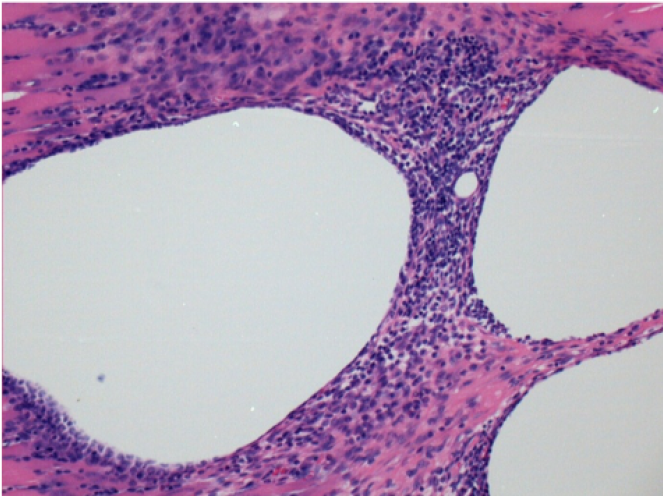

Here you may see the formation of the vacuoles which are surrounded by lymphocytes. Vacuoles are different from tissue necrosis . The presence of lymphocytes is related to the permeability of the cell membranes.